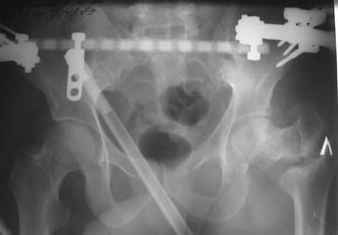

В приложении пример пациента, близкого по картине к тому, что представил Виктор (варус и смещение периферического отломка на поперечник кзади). Сделали как раз то, что Виктор исходно намеревался - аппаратная коррекция и затем гамма.